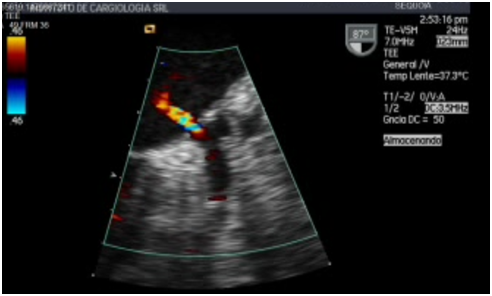

Figure 3 TEE in a projection located in the left atrial appendage using color doppler. The flow of emptying of the left atrial appendage can be observed. The color doppler shows a high speed flow.